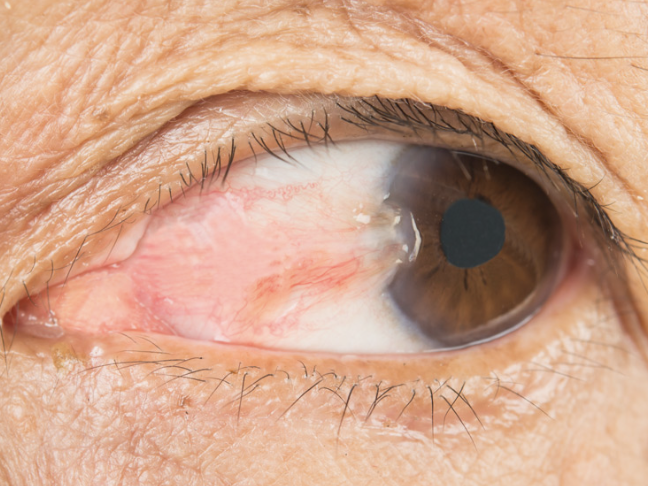

Early Pterygium

One of the 6 Corneal Abnormalities

Thickening of the bulbar conjunctiva that extends across the nasal side